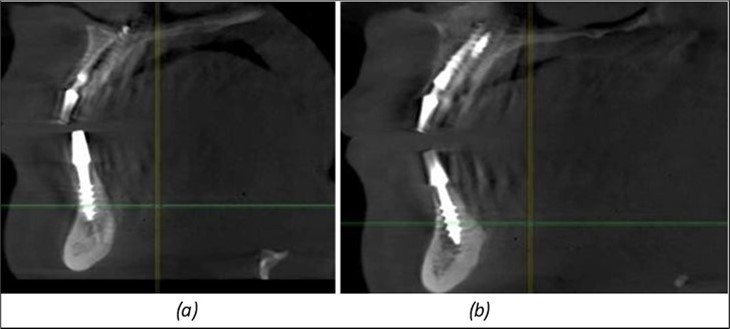

Figure 9.Implants in the pterygoid plateau area: (a) TPG implant fixed in the maxillary-sphenoid junction area, quadrant 1; (b) TPG implant fixed in the maxillary-sphenoid junction area, quadrant 2.

Implants in the pterygoid plateau area: (a) TPG implant fixed in the maxillary-sphenoid junction area, quadrant 1; (b) TPG implant fixed in the maxillary-sphenoid junction area, quadrant 2.